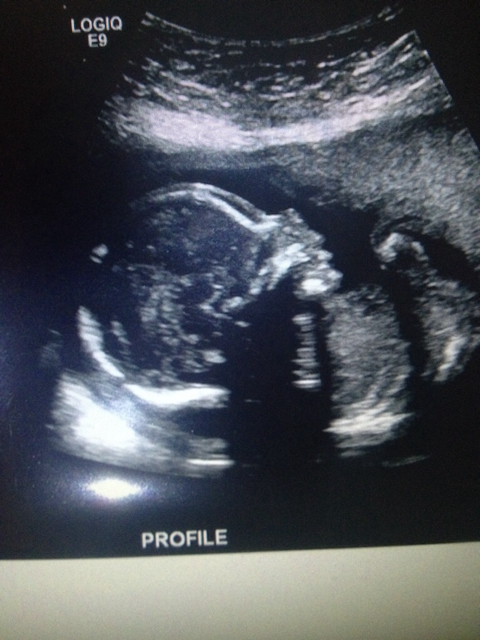

Any guesses based on skull theory? 20 week scan thank you!!!!!

Girly skull!